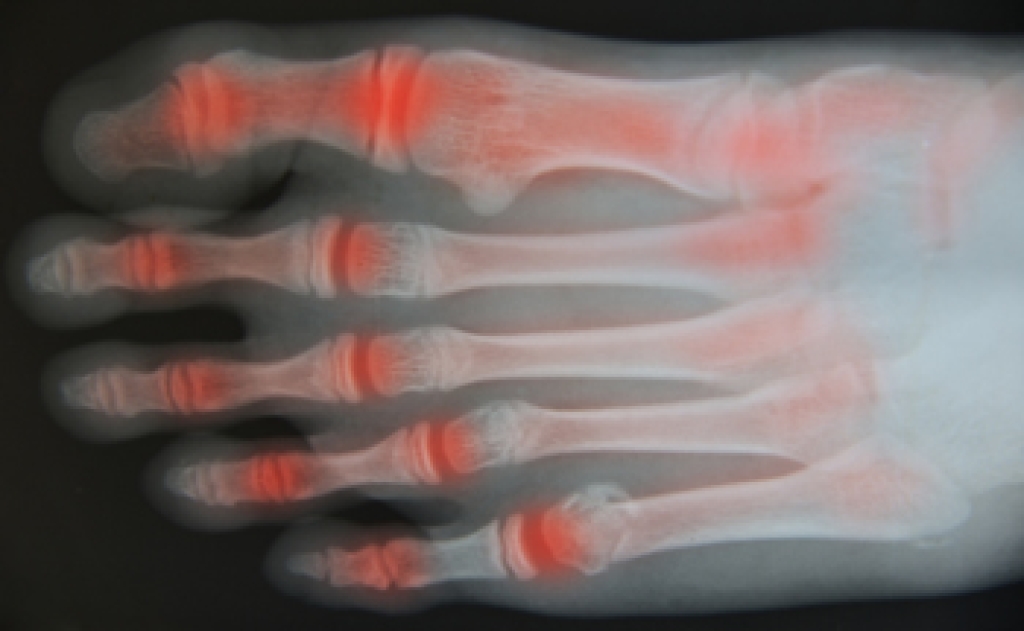

Many people begin to develop rheumatoid arthritis, or RA, when they reach their 30s or 40s. This disease is an autoimmune disorder in which the body’s immune system actually attacks the body's own tissues. This can cause pain in the joints, including those of the ankles, feet, and toes. Early symptoms of rheumatoid arthritis include fatigue, stiffness, and inflammation in the joints. Pain is generally worse when you first get up in the morning. Swelling in the lining of the joints causes pain and redness, and in most cases, affects both feet. Going up and down stairs becomes more difficult, and RA can interfere with carrying out daily activities. As rheumatoid arthritis progresses, nodules or hardened bumps may form in the joints. Eventually, the nearby bones and cartilage are affected, causing more visible deformities. In some cases, RA can harden the arteries, thereby increasing the risk of heart-related problems. For help with issues of rheumatoid arthritis in the feet, it is suggested that you consult a podiatrist.

Arthritis is a term that is commonly used to describe joint pain. The condition itself can occur to anyone of any age, race, or gender, and there are over 100 types of it. Nevertheless, arthritis is more commonly found in women compared to men, and it is also more prevalent in those who are overweight. The causes of arthritis vary depending on which type of arthritis you have. Osteoarthritis for example, is often caused by injury, while rheumatoid arthritis is caused by a misdirected immune system.